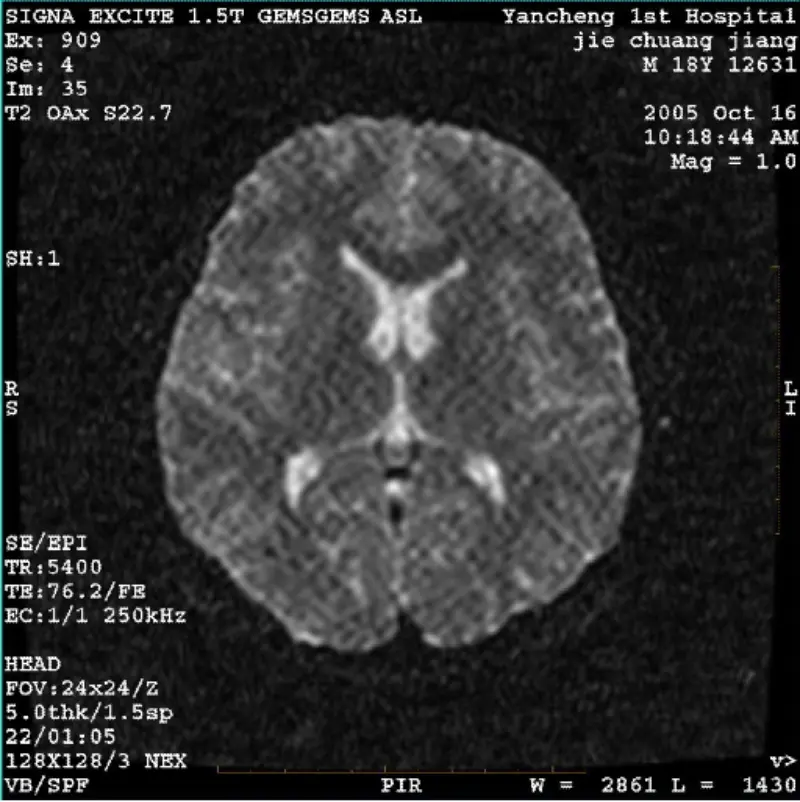

ပိုပြီးဖတ်ပါစနစ်- 1.5T Signa Twin Excite II (ဆော့ဖ်ဝဲဗားရှင်း 11.0M4) ပြဿနာ/လက္ခဏာ DWI (Zoom mode and whole mode) နှင့် fiesta (zoom mode and whole mode) ပုံများ ပါရှိခြင်း။ ကိုယ်ထည် ကွိုင် သို့မဟုတ် ဦးခေါင်းကို အသုံးပြုသည့်အခါတွင် မြင်သာထင်သာမြင်သာရှိသော ရုပ်ပုံလွှာ သို့မဟုတ် ကော်ဒရိုအရုပ်များ coil က တခ......